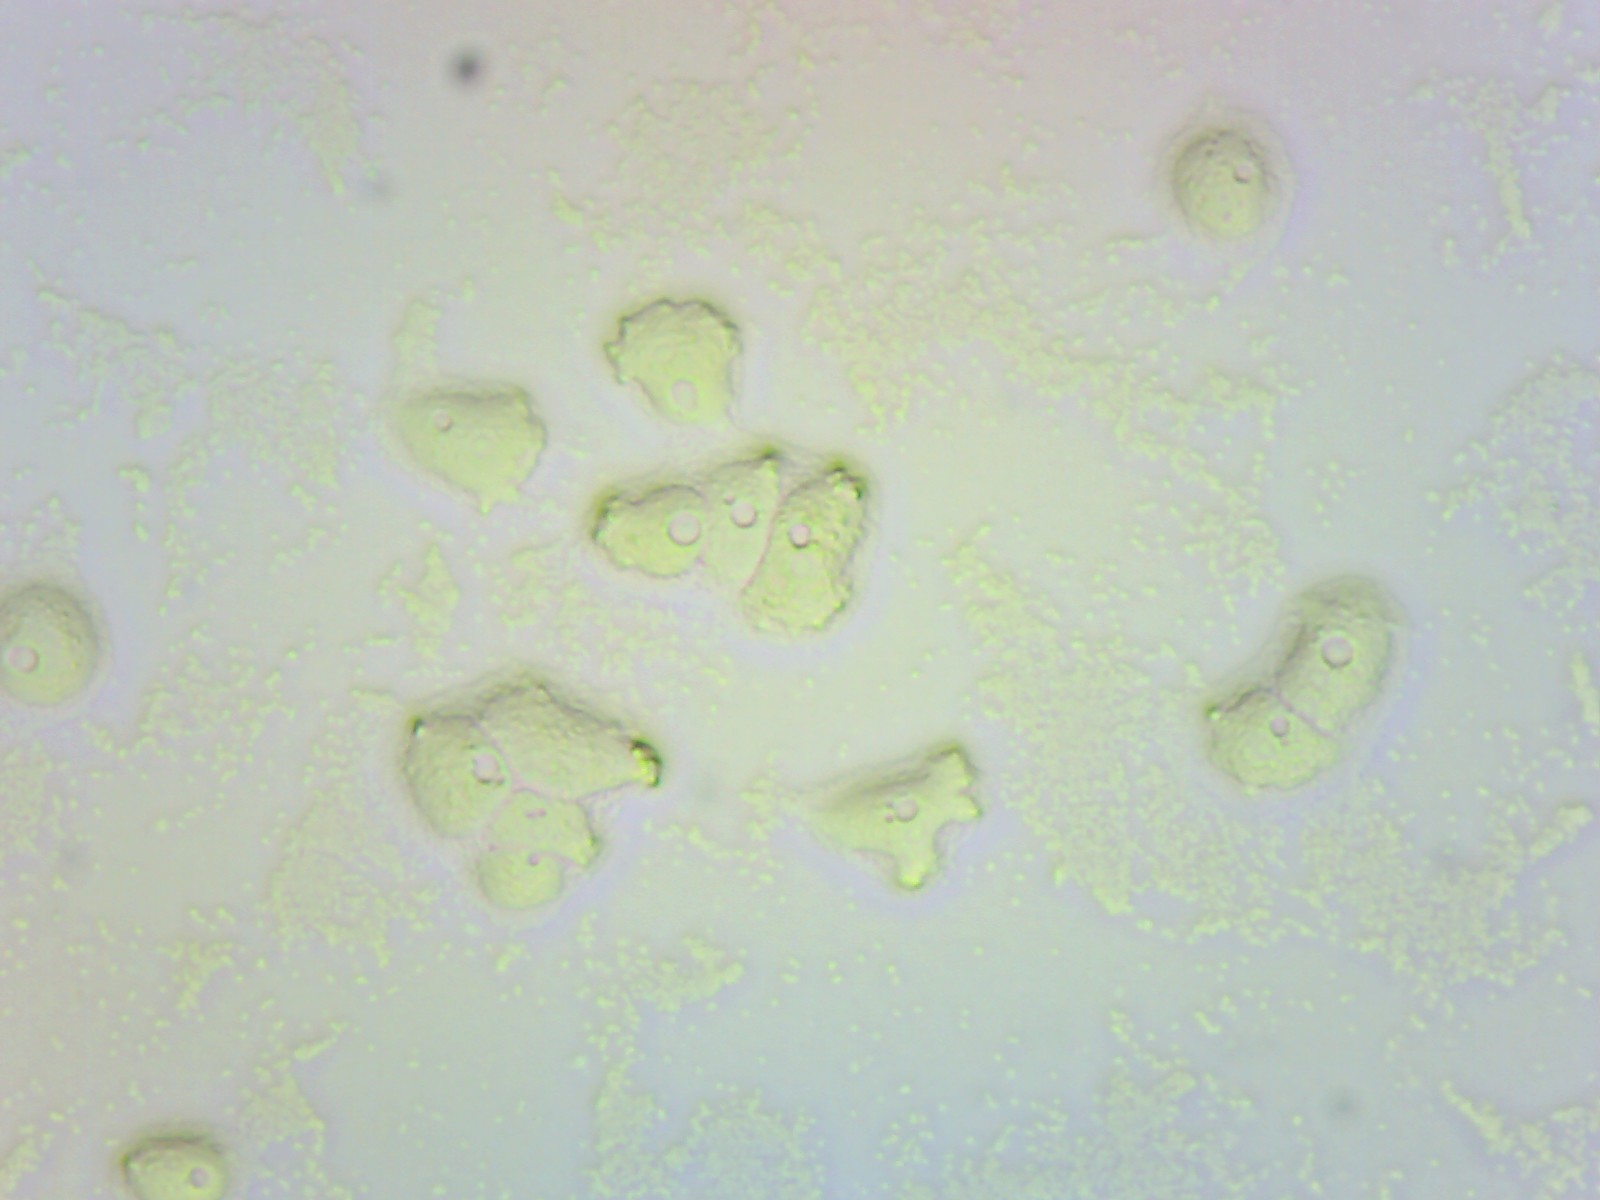

Ako vyzerá táto améba pod mikroskopom?

V laboratóriách Medirex tieto parazity diagnostikujeme priamym mikroskopickým dôkazom, kultivačným dôkazom aj farbiacimi technikami. Vieme rozlíšiť jednotlivé štádiá (trofozoit, dvojbičíkaté štádium, cysta), ktoré majú špecifickú morfológiu a štruktúru.

Mikroskopickým dôkazom možno pozorovať v odobratom likvore [mozgovomiechový mok, pozn. red.] infikovaného pacienta trofozoity [pohyblivé štádiá parazita spôsobujúce ochorenie, pozn. red.].

Podrobnejšiu štruktúru trofozoitov možno identifikovať aj po farbení podľa Giemsa. Pre parazita je po kultivácii typické rýchle rozmnožovanie. V tekutom prostredí sa dajú pozorovať dvojbičíkaté štádiá.

A po spotrebovaní živín (inaktivovaných baktérií na kultivačnej pôde) dochádza k tvorbe cýst. Tie sú odolné voči nepriaznivým životným podmienkam.